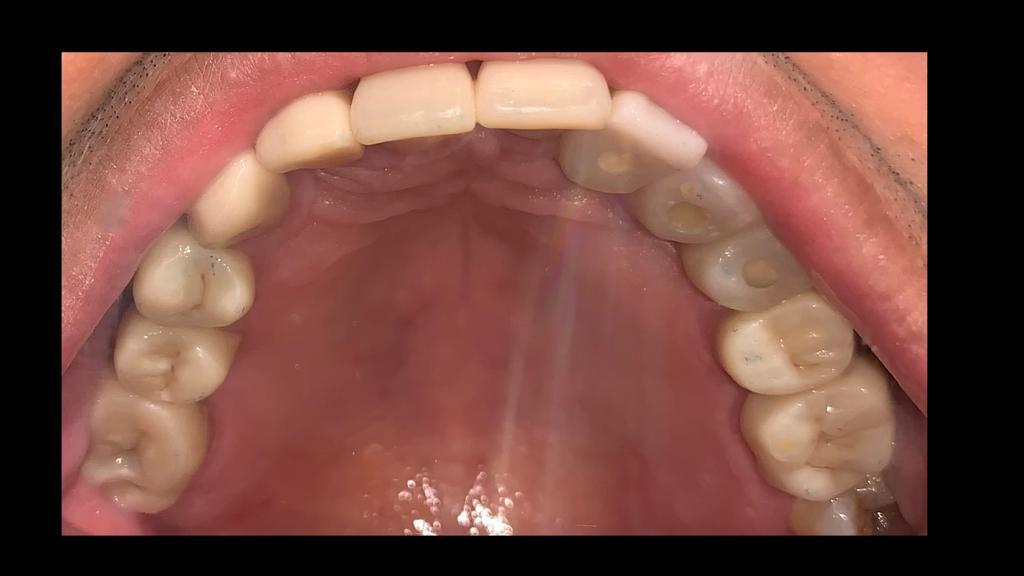

Fase 3: Diagnóstico inicial maxilar superior

Rehabilitación Oral - Diagnóstico Superior

Estado inicial del paciente con ausencia dental severa en maxilar superior, afectando función masticatoria y estética.